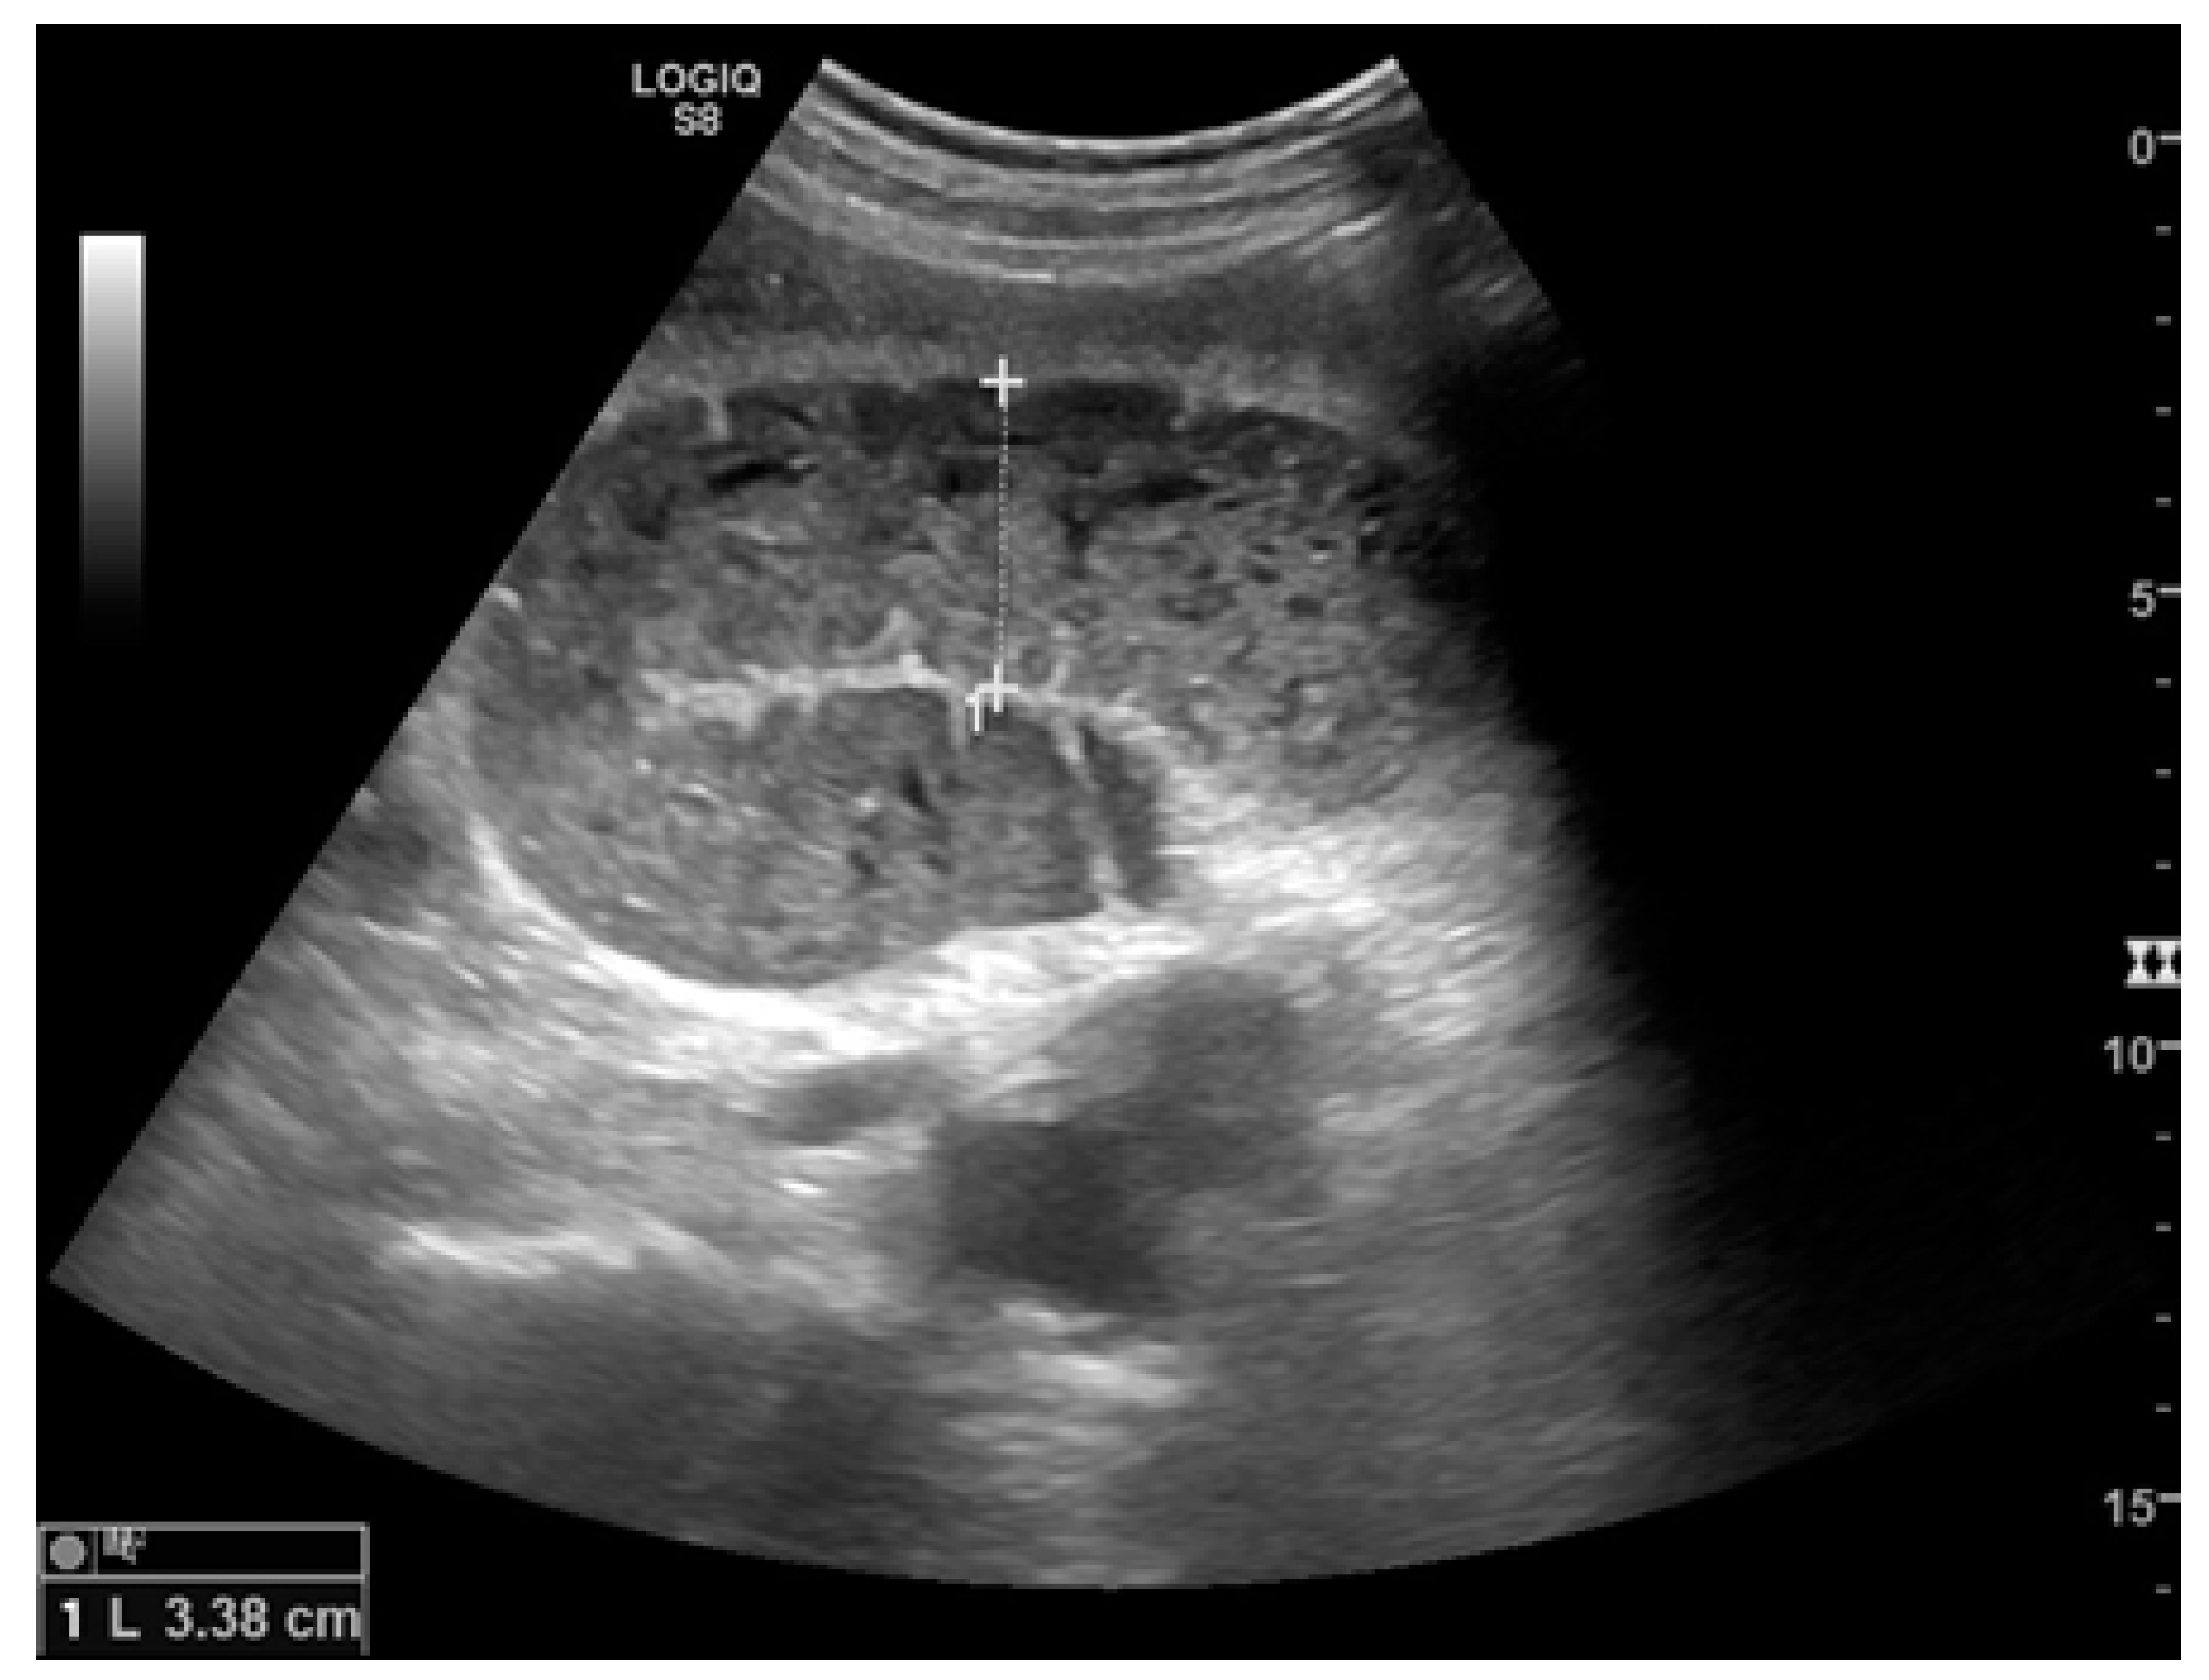

Figure 2.

A dilated small bowel loop with a caliber of more than 3 cm (dotted line) with trapped feces defines a ‘small bowel feces sign’. Bowel walls appear thin, and the folds flatten.